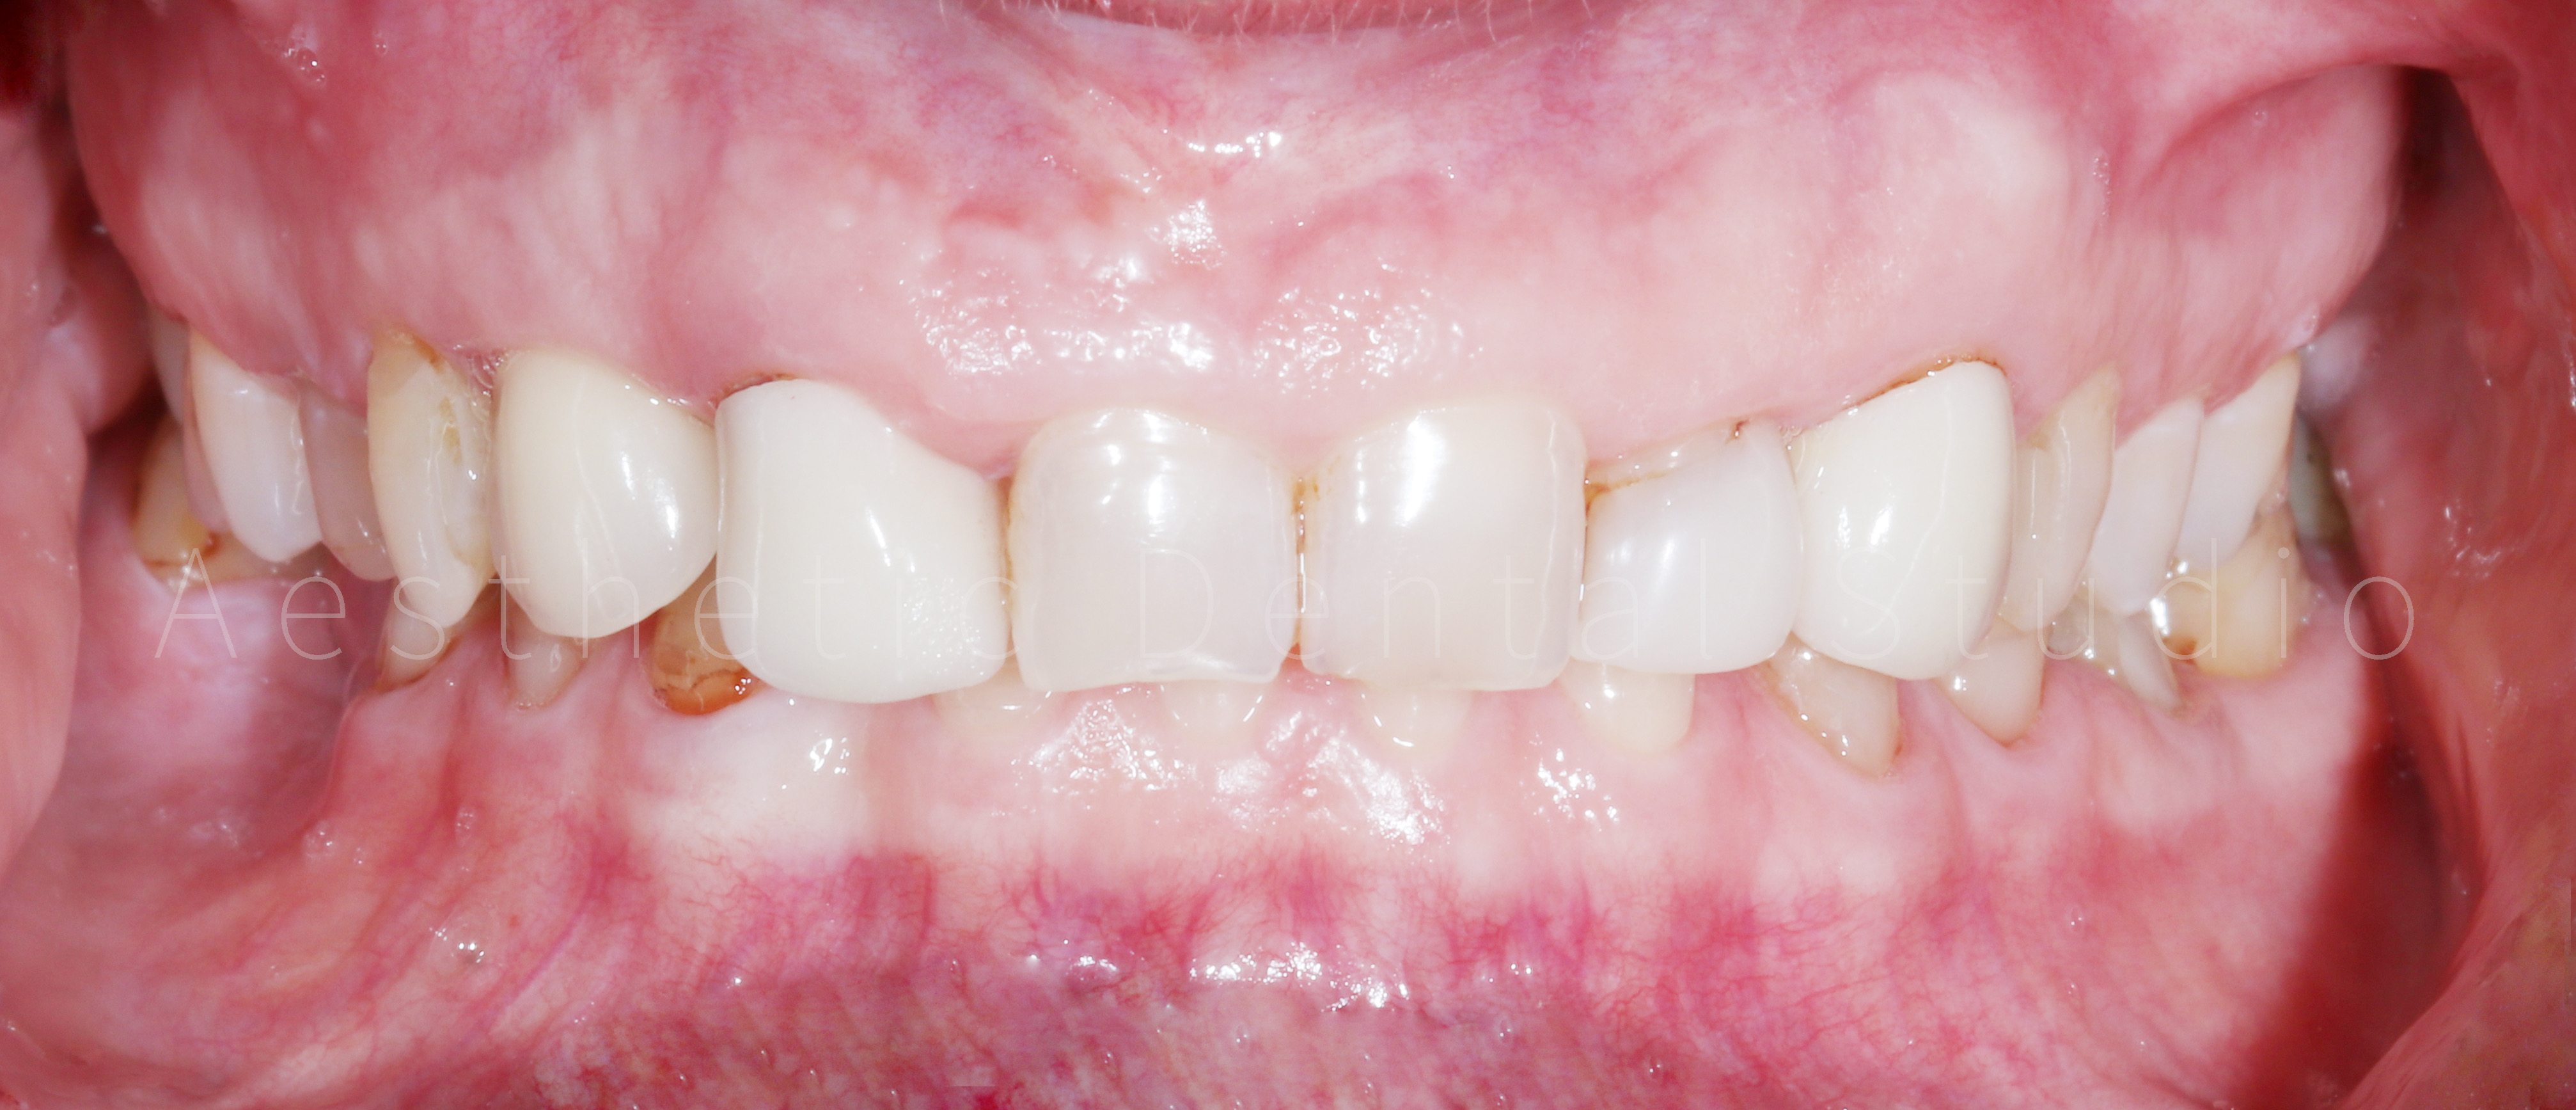

Το τελικό χαμόγελο ήταν φυσικό, φωτεινό και αρμονικό, αναδεικνύοντας τα χαρακτηριστικά της ασθενούς, χωρίς υπερβολές. Η θεραπεία ολοκληρώθηκε μέσα σε 10 ημέρες, συνδυάζοντας αισθητική αριστεία, λειτουργική σταθερότητα και άριστο χρονοπρογραμματισμό. Η ασθενής αναχώρησε από την Καλαμάτα με ένα εντελώς ανανεωμένο χαμόγελο, απολαμβάνοντας τη μοναδική εμπειρία ενός αισθητικού ταξιδιού οδοντιατρικής φροντίδας στην Ελλάδα